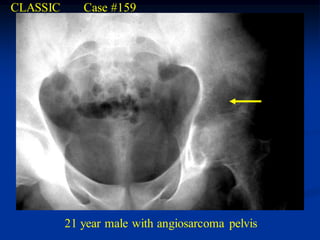

CLASSIC      Case #159

21 year male with angiosarcoma pelvis

Progressive disease at a later date

CT scan above sciatic notch level

CT scan just below the sciatic notch

CT scan at femoral head level

tumor

Coronal T-1 MRI

Axial T-1 MRI

Photomic

Higher power